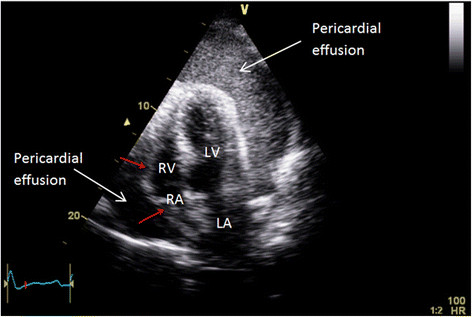

Step 1 – Identify Effusion

Use:

• Apical 4-chamber

• Parasternal long-axis

• Subxiphoid

Choose the shortest needle-to-fluid path without intervening lung or coronary vessels.

Step 4 – Confirm Pericardial Entry

• Fluid aspiration

• Agitated saline bubbles in pericardial space

• Hemodynamic improvement